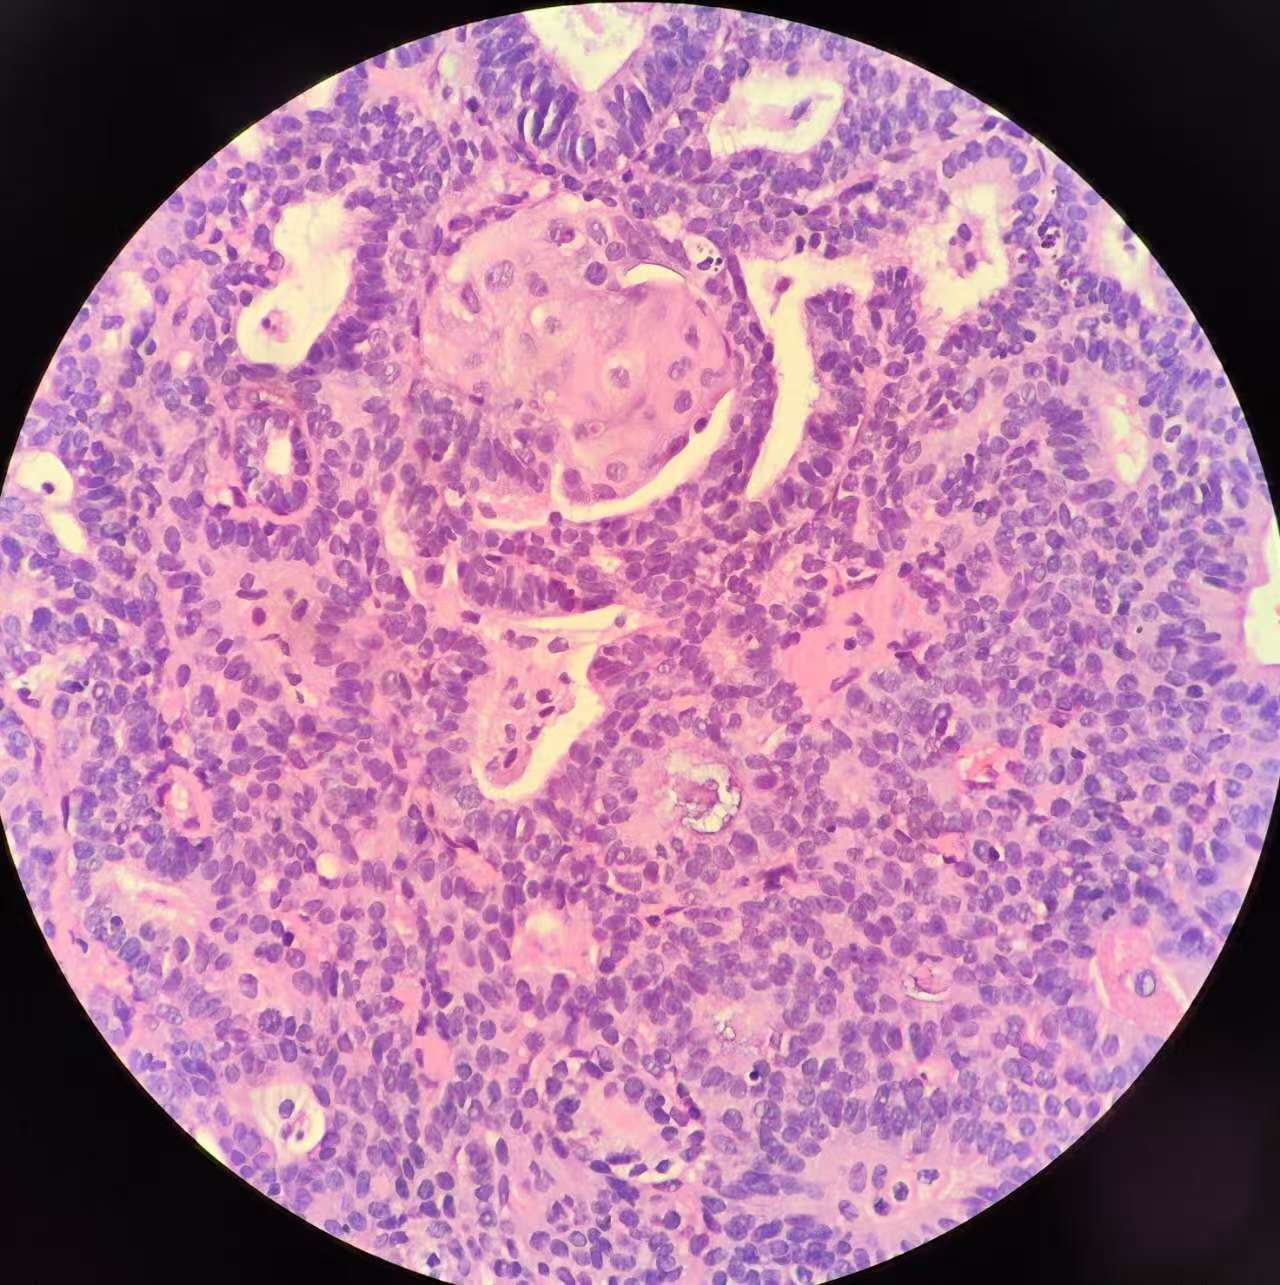

性别

女

年龄

51岁

临床诊断

子宫 内膜息肉?

一般病史

绝经三年,近期阴道出血,宫腔镜见后壁槽杂样组织,质脆

标本名称

子宫内膜诊刮

大体所见

灰红碎组织1堆

复杂性增生?部分区域腺体融合似成实性,癌?局部内膜腺体鳞化还是宫颈鳞上皮病变(第1张图和最后一张)?

考虑子宫内膜样腺癌,伴有鳞状分化。